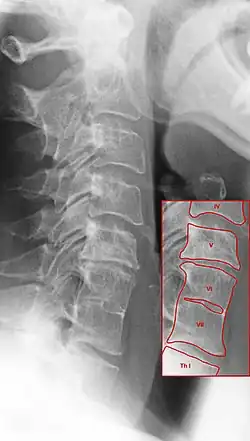

Radiologische Differenzialdiagnose

Auch die verschleißbedingte Osteochondrose der Wirbelsäule bedingt eine Verschmälerung der Zwischenwirbelräume. Die Abbildung unten zeigt die Unterschiede: Die Osteochondrose zwischen Halswirbelkörper V und VI weist den betroffenen Wirbel überragende Exophyten auf. Zwischen den Wirbeln VI und VII dagegen sind solche Auswulstungen nicht zu sehen. Die dort sichtbare Verbindung der Wirbelkörper ist anlagebedingt und hat nichts mit Verschleiß zu tun. Tendenziell ist die Wirbelsäule dort sogar schmaler (deutlich zu sehen in der Aufnahme der Halswirbelsäule im Bild oben).